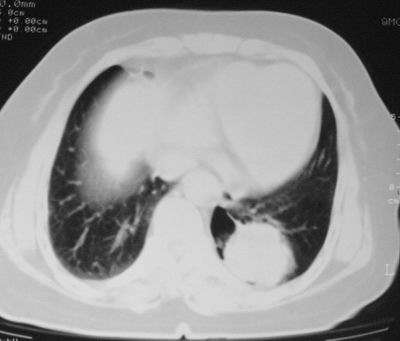

患者,女,64岁,4年前左腮腺"多形性"腺瘤手术治疗史.现复查胸部ct见左下肺块状影,该影与原左腮腺手术是否有联系?

本次复查胸部ct

左下肺软组织块影,有分叶、毛刺、空泡及胸膜牵拉征,左下肺周围性肺癌。

左肺下叶周围型肺癌,支持!(软组织肿块+分叶+毛刺+空泡+胸膜凹陷征)

左下肺软组织密度影,可见分叶,边缘可见毛刺征,胸膜增厚,强烈要求左下肺周围型肺癌

左下肺后基底段实性肿块,周围有毛刺,病变周围有肺气肿,与降主动脉间有条带状影相连,病灶4年前查体发现,纵隔内未见肿大淋巴结。考虑.肺隔离症,建议增强扫描与周围型肺癌鉴别。